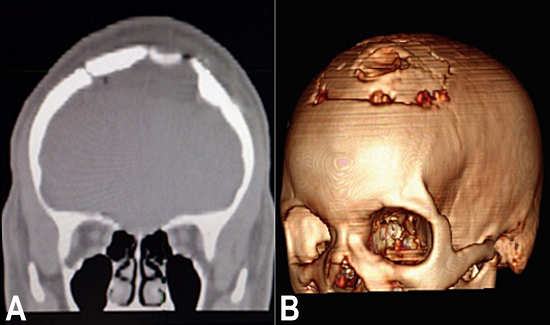

The histological exam of the lesion confirmed the diagnosis of an arachnoid cyst. The patient was prescribed antibiotics, an anticonvulsant, and an analgesic during the postoperative period. A CT scan performed 1 week after surgery demonstrated the absence of the cyst and adequate surgical reconstruction (Figure 5A and 5B).